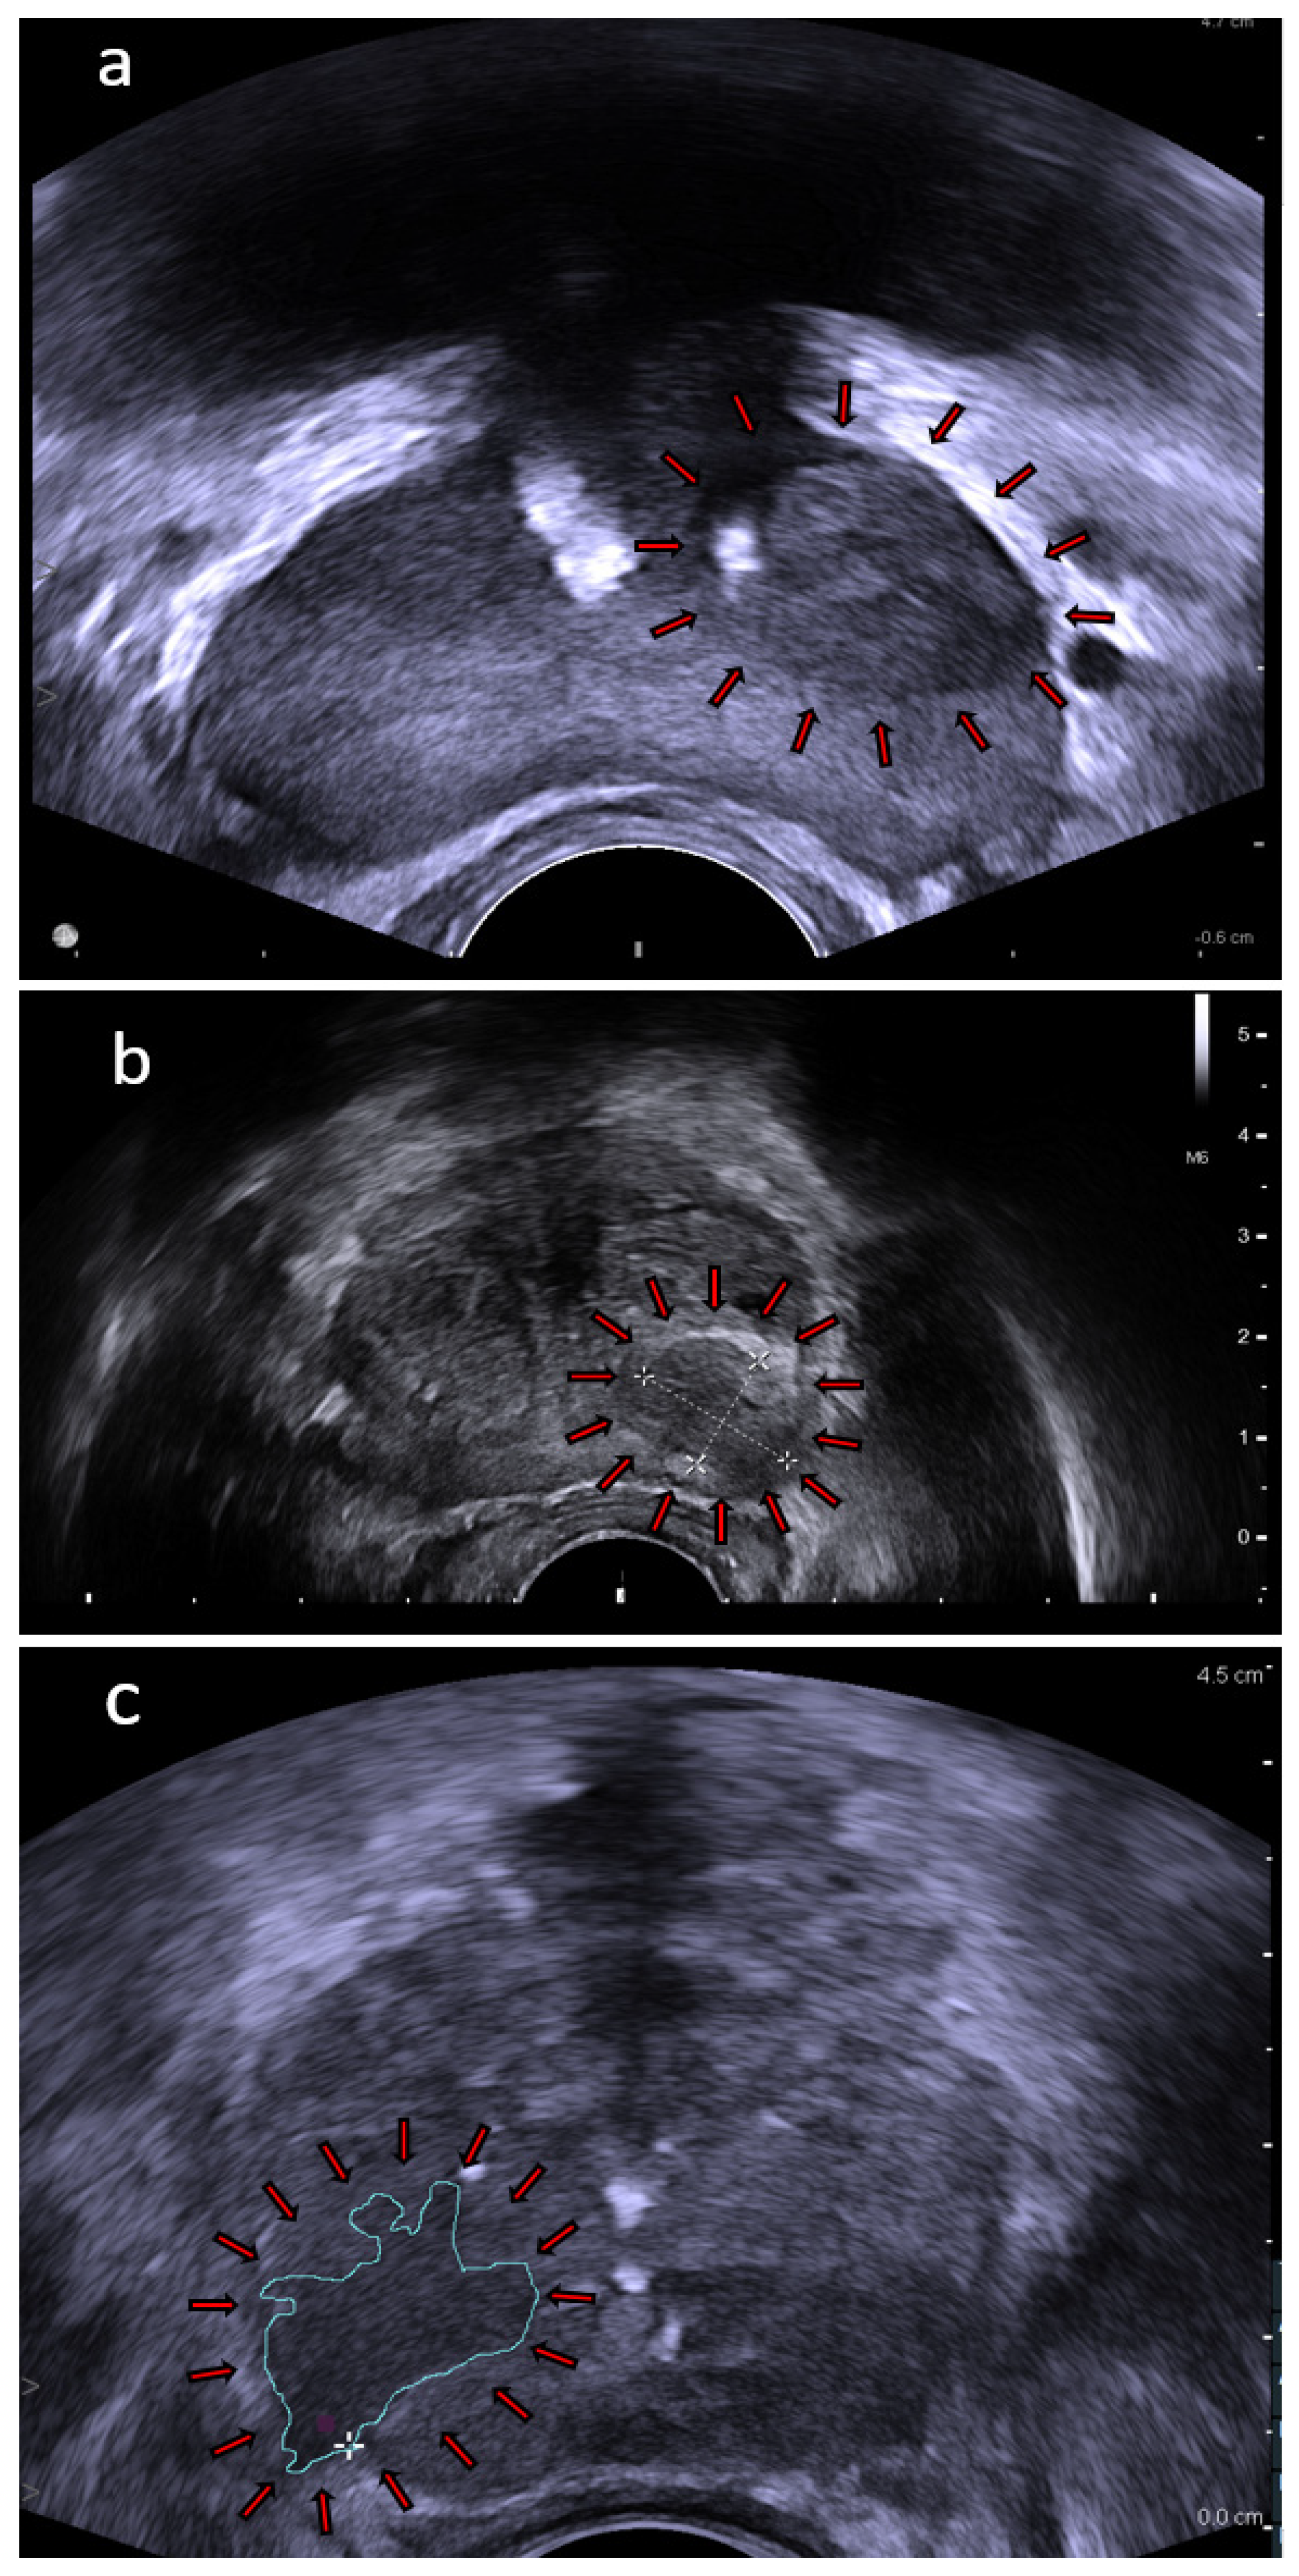

4.1. High Frequency Micro-Ultrasound

4.3. Shear-Wave Elastography

4.4. Multiparametric Ultrasound